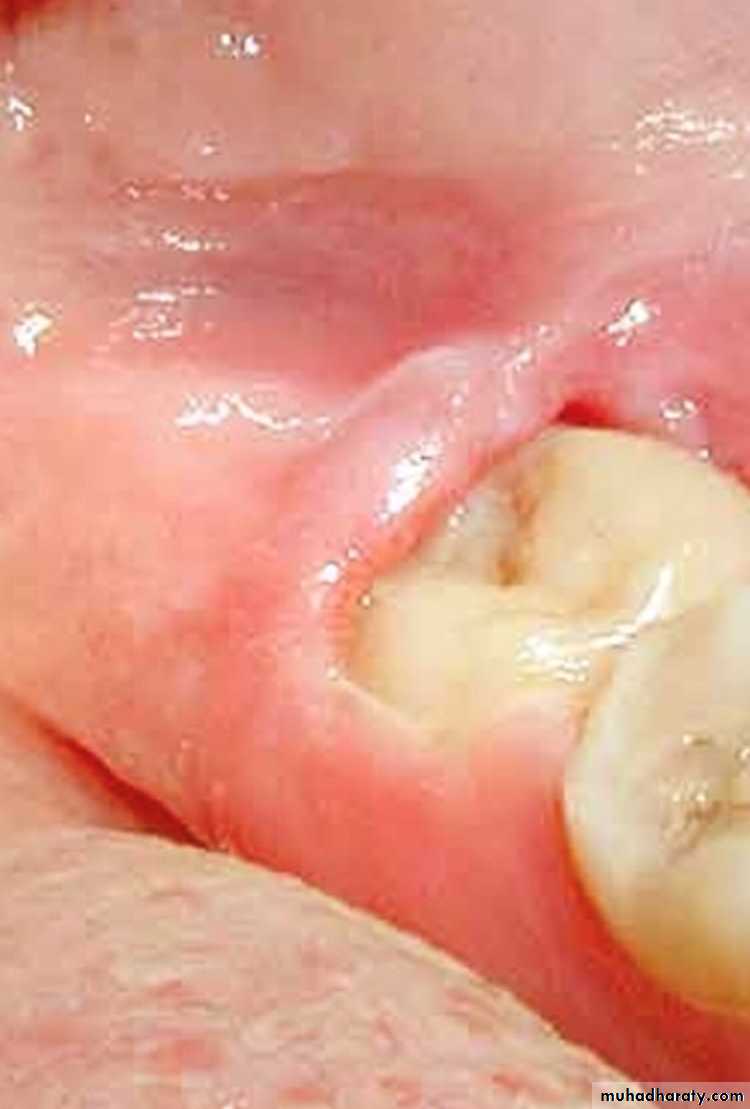

Periodontal abscesses are associated with poorly localized dull pain, adjacent teeth are tender, clenching the teeth, which are usually vital, characteristically brings relief. Mobility of teeth, pathologic sinuses, and evidence of periodontitis are often presentPericoronitis :

Pericoronitis produces rapid onset of soreness or pain in the soft tissues surrounding the crown of a partially irrupted tooth.In the case of impacted third molars particularly the lower ones this soreness is a associated with pain on swallowing and trismus these symptoms are particularly sever in cases of acute pericoronitis. Subacute pericoronitis Is also associated with soreness, pain on swallowing, and trims but their degree severity is milder than that of the acute phase of the disease.